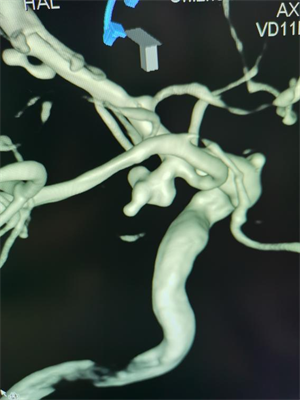

颅内动脉瘤破裂的“生死逆转战”

当天上午,64 岁的袁女士因突发剧烈头痛、呕吐急诊入院。CT显示蛛网膜下腔出血,进一步行头颈CTA检查确诊为颅内动脉瘤破裂。这是一种死亡率极高的疾病。神经内科介入团队在上级专家的指导下,迅速实施急诊栓塞手术,通过微导管将弹簧圈精准填入瘤体,成功栓塞破裂的动脉瘤。此类手术要求极高的精细度,术中需平衡栓塞效果与血管保护,我院团队的快速响应为患者赢得了生机。目前,袁女士神志清楚,病情稳定。

△图一:手术前可见后交通动脉瘤合并多个突起

△图二:手术后动脉瘤已经栓塞,造影不可见